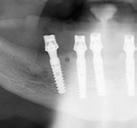

Exploración radiológica

Mediante CBCT constatamos atrofias óseas severas y disminución de soporte óseo periodontal en relación con las piezas dentales.

A tenor del estado oral proponemos múltiples opciones terapéuticas, consensuando entre paciente y facultativos una rehabilitación implantoprotésica fija superior e inferior. Debido a la lejanía de la residencia de la paciente, y motivados por las necesidades estéticas que esta exige, consideramos realizar una carga inmediata impresa con resina definitiva el mismo día de la cirugía. Tras el escaneado intraoral con el escáner Dexis IS3700 (Figuras 7 y 8) y realización de CBCT, subimos los ficheros a la plataforma Bego Guide,

31 Gaceta Dental · N o 366 | Mayo 2024 Caso clínico. CIENCIA Y CLÍNICA

Figura 3. Visión intraoral oclusal mandibular. Figura 4. Visión intraoral frontal. Figura 1. Visión intraoral oclusal maxilar. Figura 2. Visión lateral izquierda intraoral. Figura 7. Escaneado intraoral maxilar con Dexis IS3700. Figura 8. Escaneado intraoral mandibular con Dexis IS3700. Figura 5. Visión extraoral lateral sonrisa.

32 CIENCIA Y CLÍNICA. Caso clínico Gaceta Dental · N o 366 | Mayo 2024

Figura 6. Visión extraoral frontal sonrisa.

procediendo a realizar una solicitud de encargo a través de un formulario. Antes de 72 horas recibimos una propuesta terapéutica. En ella se facilitan vistas 3D detalladas, así como valoraciones y consideraciones a tener en cuenta durante el fresado y la inserción de los implantes (Figuras 9 a 19). Decidimos realizar extracción de todas las piezas remanentes, dada su nula viabilidad a corto-medio plazo y en Bego (a través del portal) proponen mantener 3 piezas (las más viables técnicamente) en cada arcada para proporcionar el anclaje óptimo de la

férula. Tras la aceptación del caso envían a la clínica la férula quirúrgica junto con un claro protocolo de secuencia de fresado.